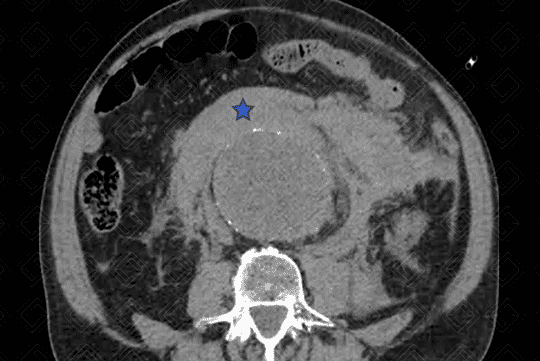

Texto alternativo para a imagem Figura 3. Créditos: Dra. Elazir Mota - Rio de Janeiro/RJ

Descrição das figuras 1, 2 e 3: Sinais de ruptura de aneurisma da aorta abdominal com extenso hemoperitônio. Hematoma hiperdenso mais bem apreciado nas fases sem contraste (asteriscos - figuras 1 e 2), que se estende ao espaço pararrenal e perirrenal esquerdo. Após a administração do contraste, observa-se extravasamento ativo do mesmo (seta vermelha - figura 3). [cms-watermark]